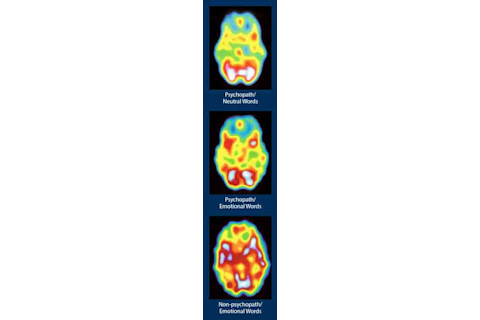

精神病态者的大脑扫描在面对中性词和情感词时变化不大,与非精神病态者的大脑相比,其大脑活动也少得多。(图片来源:罗伯特·黑尔惠允)

在连接到追踪大脑活动的脑电图(EEG)设备上,研究参与者被要求观看中性词或情感词——桌子、书桌、地毯、尸体、蛆虫、折磨——然后是打乱的词。“对于情感词,大多数人可以非常快速、准确地辨别单词和打乱的词,”黑尔说,“但精神病态者对情感词和中性词的反应是相同的。没有情感上的涡轮增压。这令人震惊。1991年,我们向《科学》杂志提交了这篇论文,但最初被拒绝了,因为编辑们认为这些人不可能真实存在。”

《科学》杂志最终在当年晚些时候发表了这篇论文,几年后,在首次精神病态脑成像研究中也得到了复制,那是黑尔与布朗克斯退伍军人事务医疗中心药物滥用诊所合作的成果。